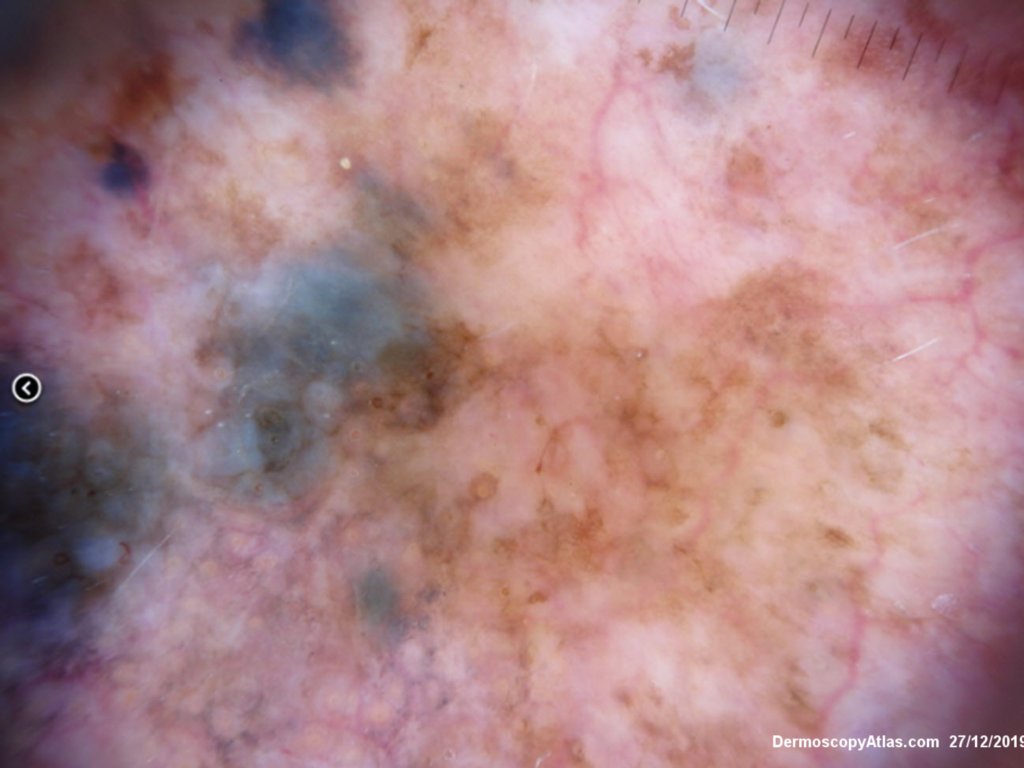

Description: Background brown lesion with blue macules and papules developing

This elderly man had a preceeding lentigo maligna but subsequently developed in transit metastases as shown by the blue macules and papules on his cheek. He was treated with Keytruda. PET scan was negative for spread elsewhere.